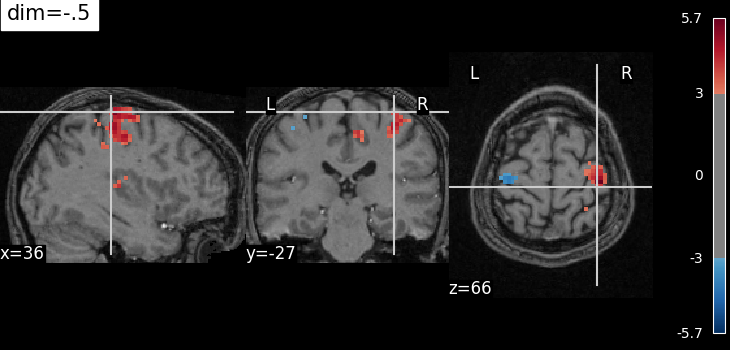

The dim argument controls the contrast of the background.

dim modifies the contrast of this image: dim=0 leaves the image unchanged, negative values of dim enhance it, and positive values decrease it (dim the background).

Plotting with enhancement of background image with dim=-.5¶

from nilearn.plotting import plot_stat_map, show

cut_coords = (36, -27, 66)

plot_stat_map(

localizer_tmap_filename,

bg_img=localizer_anat_filename,

cut_coords=cut_coords,

threshold=3,

title="dim=-.5",

dim=-0.5,

)

<nilearn.plotting.displays._slicers.OrthoSlicer object at 0x7f1ee82de200>